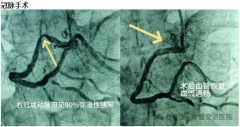

今日凌晨,患者赵某因突发胸闷、胸部压榨样疼痛,于凌晨12点被紧急送至我院急诊科...[全文]

灵璧安浈医院介入科成立于2023年11月4日,是与郑州大学介入研究所共同打造,是集心血...[全文]